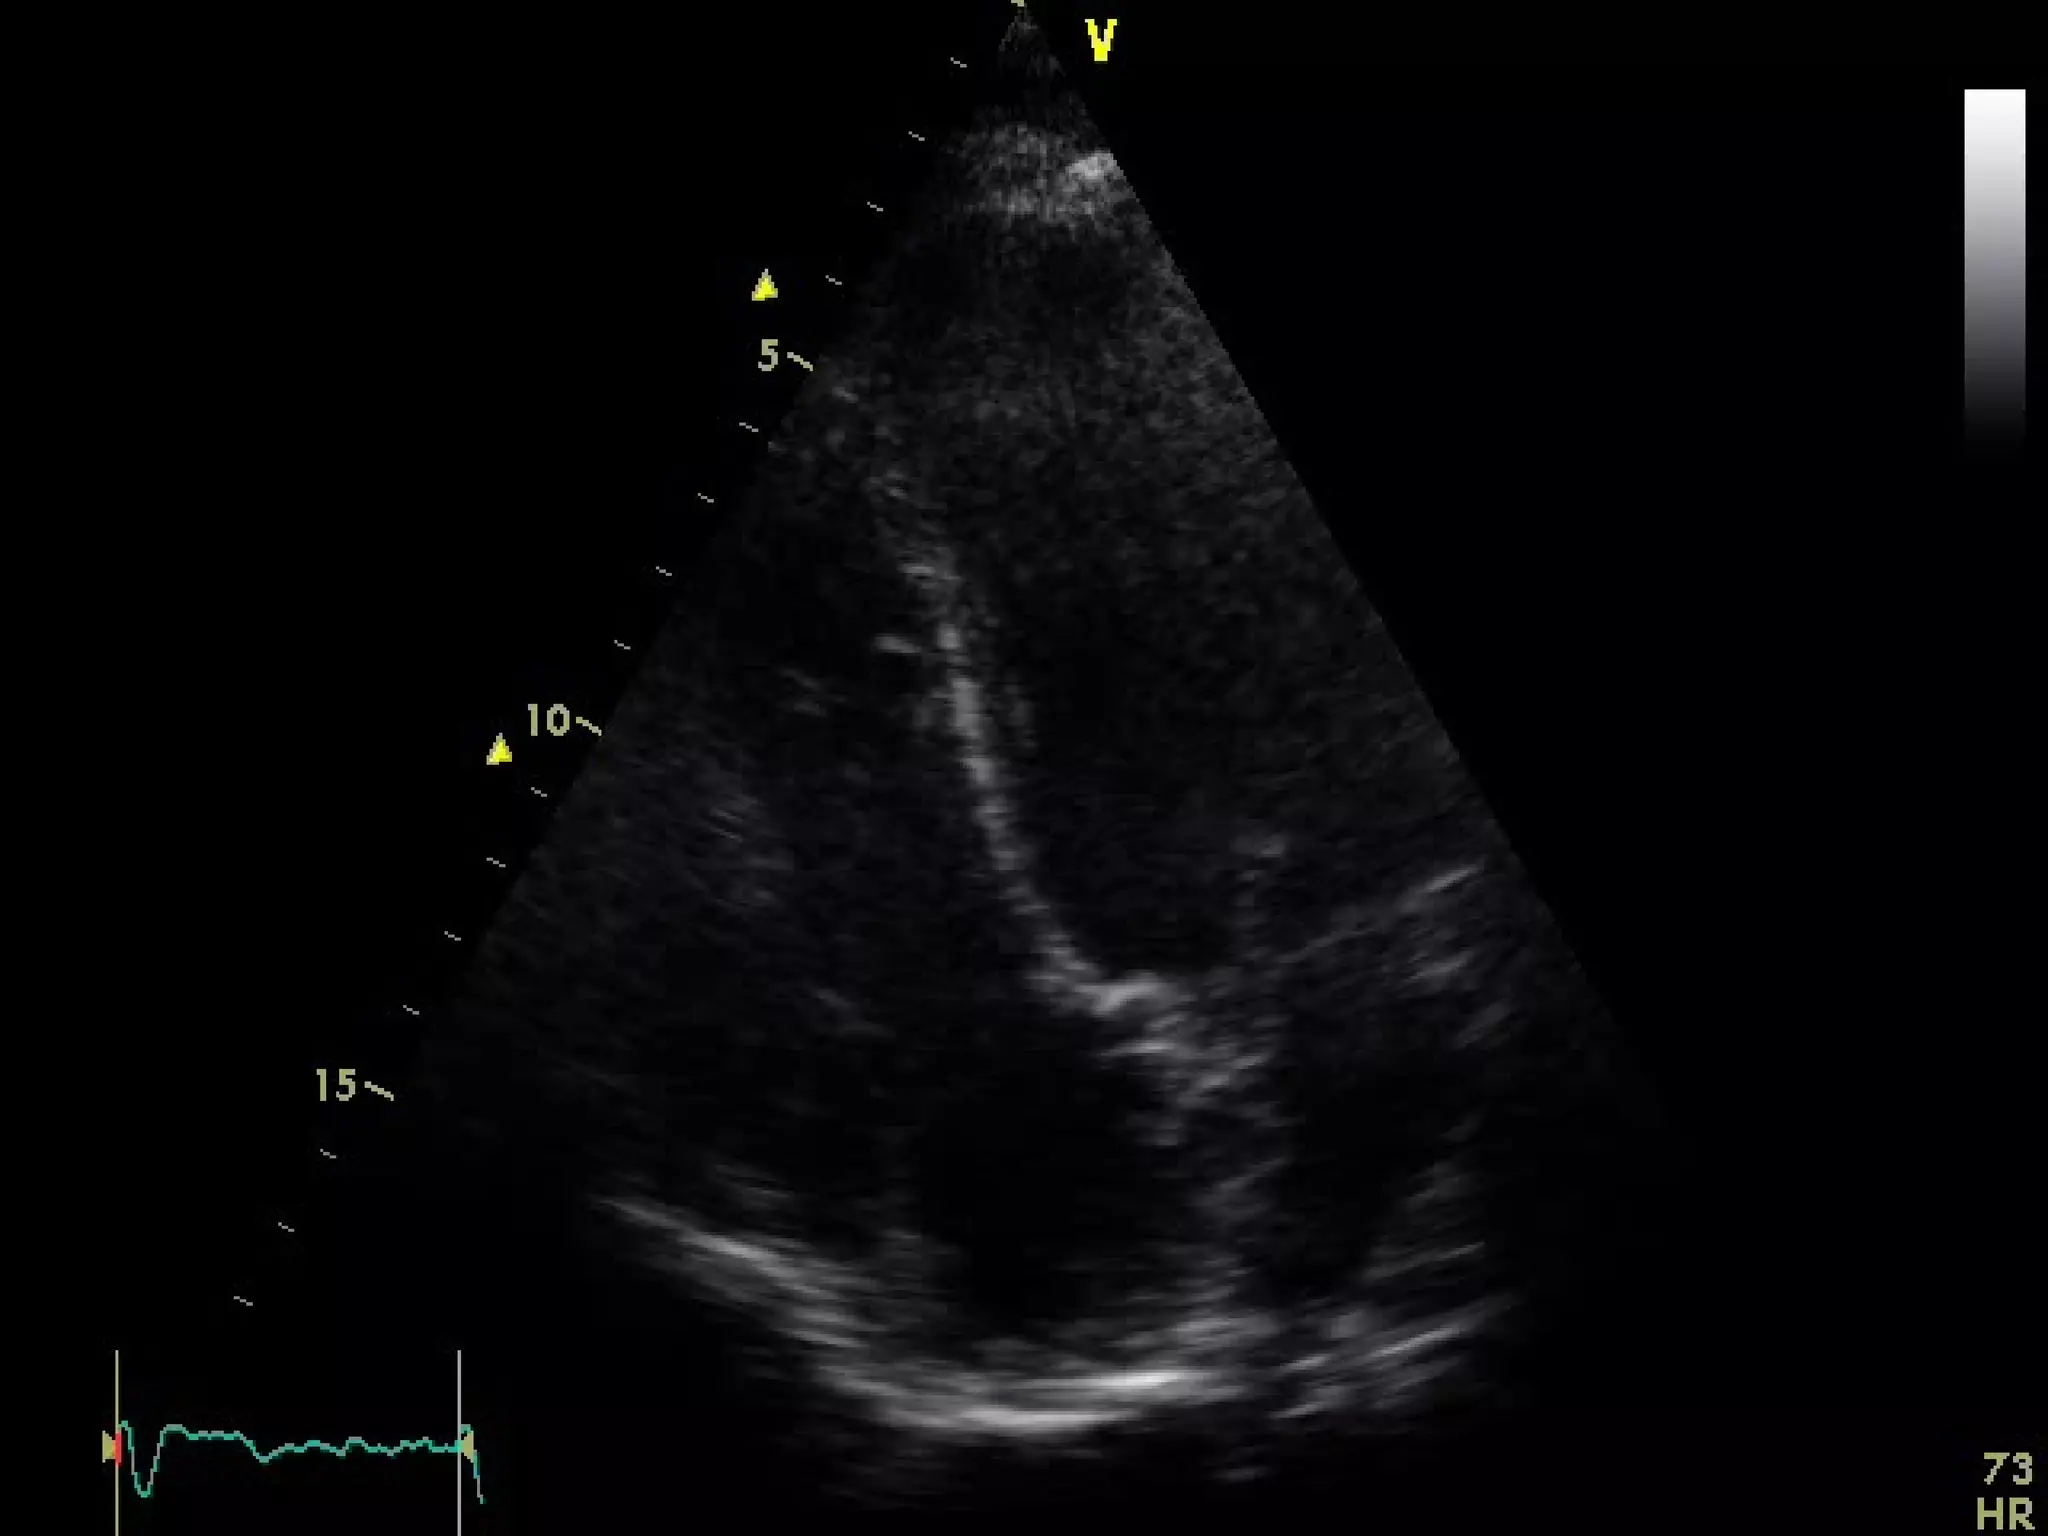

In the apical four-chamber view, all four

chambers of the heart may be seen The left

ventricle appears as a truncated ellipse,RV

triangular with the interventricular septum, apex

formed by LV, and lateral walls visualized.

With the patientmaintained in the left lateral decubitus position, the transducer is placed near the apex of the heart with an inferior orientation In the apical four-chamber view, all four chambers of the heart may be seen The left ventricle appears as a truncated ellipse,RV triangular with the interventricular septum, apex formed by LV, and lateral walls visualized. Apical four-chamber